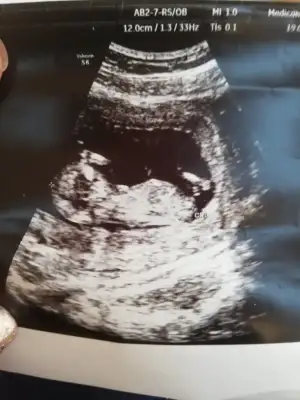

Ay baya minyatür insan yaa masallah maşallahhhKızlar doktordan cıktım ense kalınlıgı iyi burun kemiği iyi ikili yaptırdım cuma cıkıyo sonuç. Ölçüm yapmakta zorlandı doktor seninki fazla hareketli diyo☺

Kizz bu yaaaKızlar doktordan cıktım ense kalınlıgı iyi burun kemiği iyi ikili yaptırdım cuma cıkıyo sonuç. Ölçüm yapmakta zorlandı doktor seninki fazla hareketli diyo☺